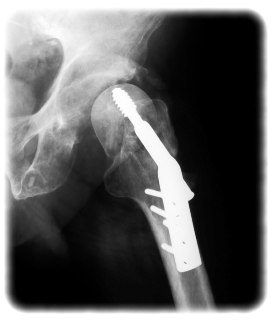

• Development and sales of implant devices and instruments for use in trauma surgery in closelycooperation with highly-regarded doctors with he target